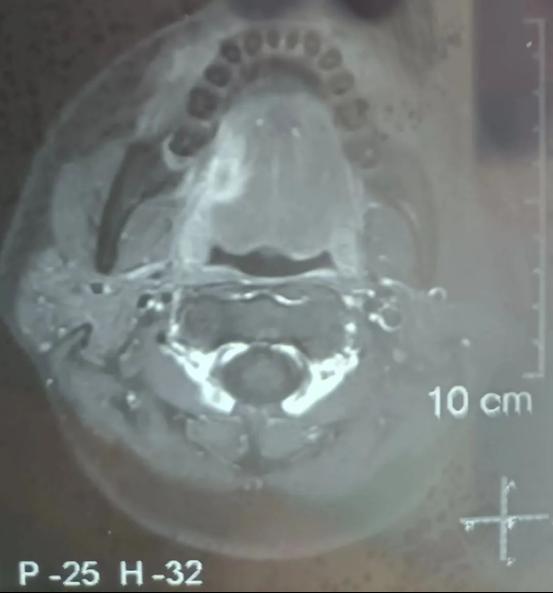

今年34岁的患者因“右舌缘疼痛性包块3+月”到小艾电竞 口腔颌面外科住院治疗,完善病理活检及颌面部MRI检查后明确为右舌缘鳞状细胞癌,临床分期为cT3N0M0,且肿瘤已侵犯右侧舌外肌。

术前图

患者颌面部MRI影像